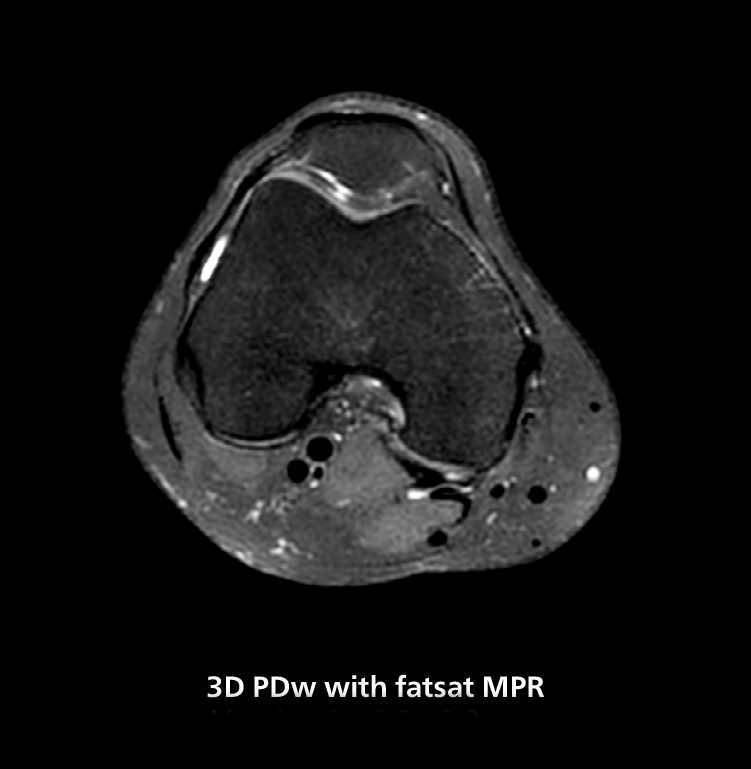

The isotropic high resolution 3D sequence in this MRI case allows for reformatting to obtain other orientations with high quality. Acquired on the MR 5300 system.